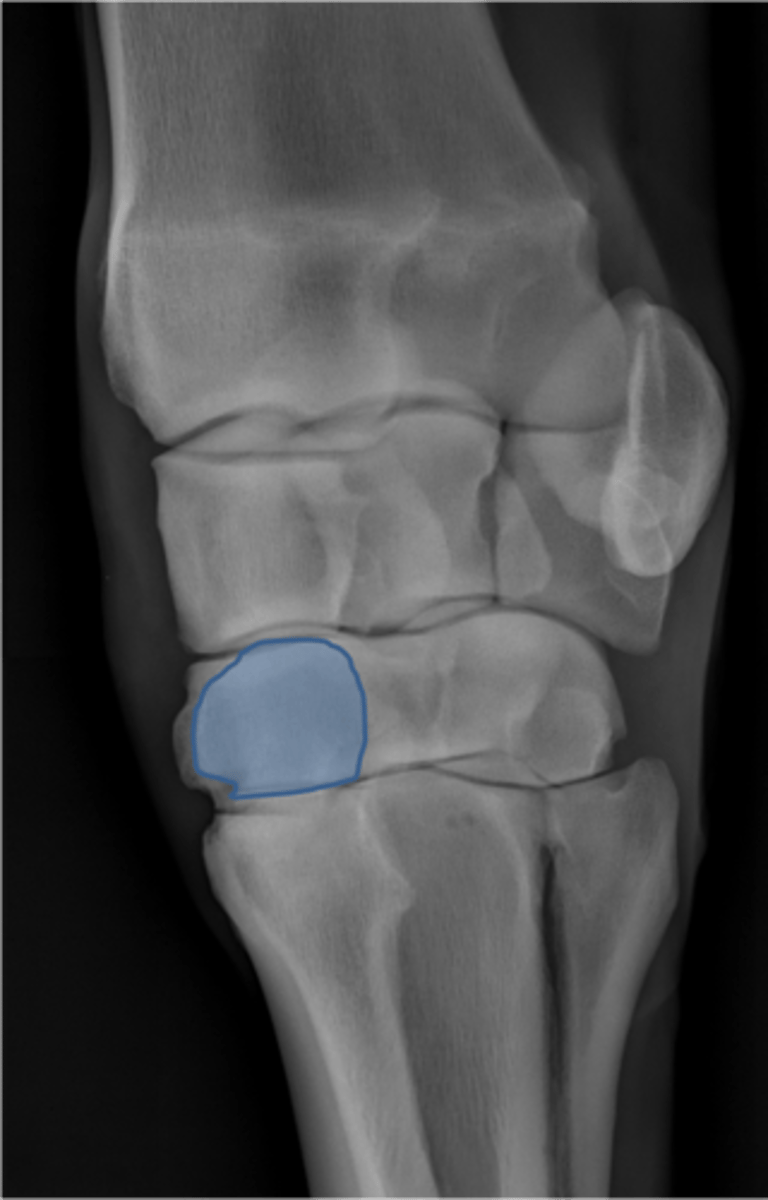

Carpus, lateral

ID joint and view

Antebrachiocarpal joint

Middle carpal joint

Carpometacarpal joint

Radial carpal bone

Intermediate carpal bone

Ulnar carpal bone

Third carpal bone

Second carpal bone

Fourth carpal bone

Accessory carpal bone

Second metacarpal (medial splint)

Fourth metacarpal (lateral splint)

Cannon bone